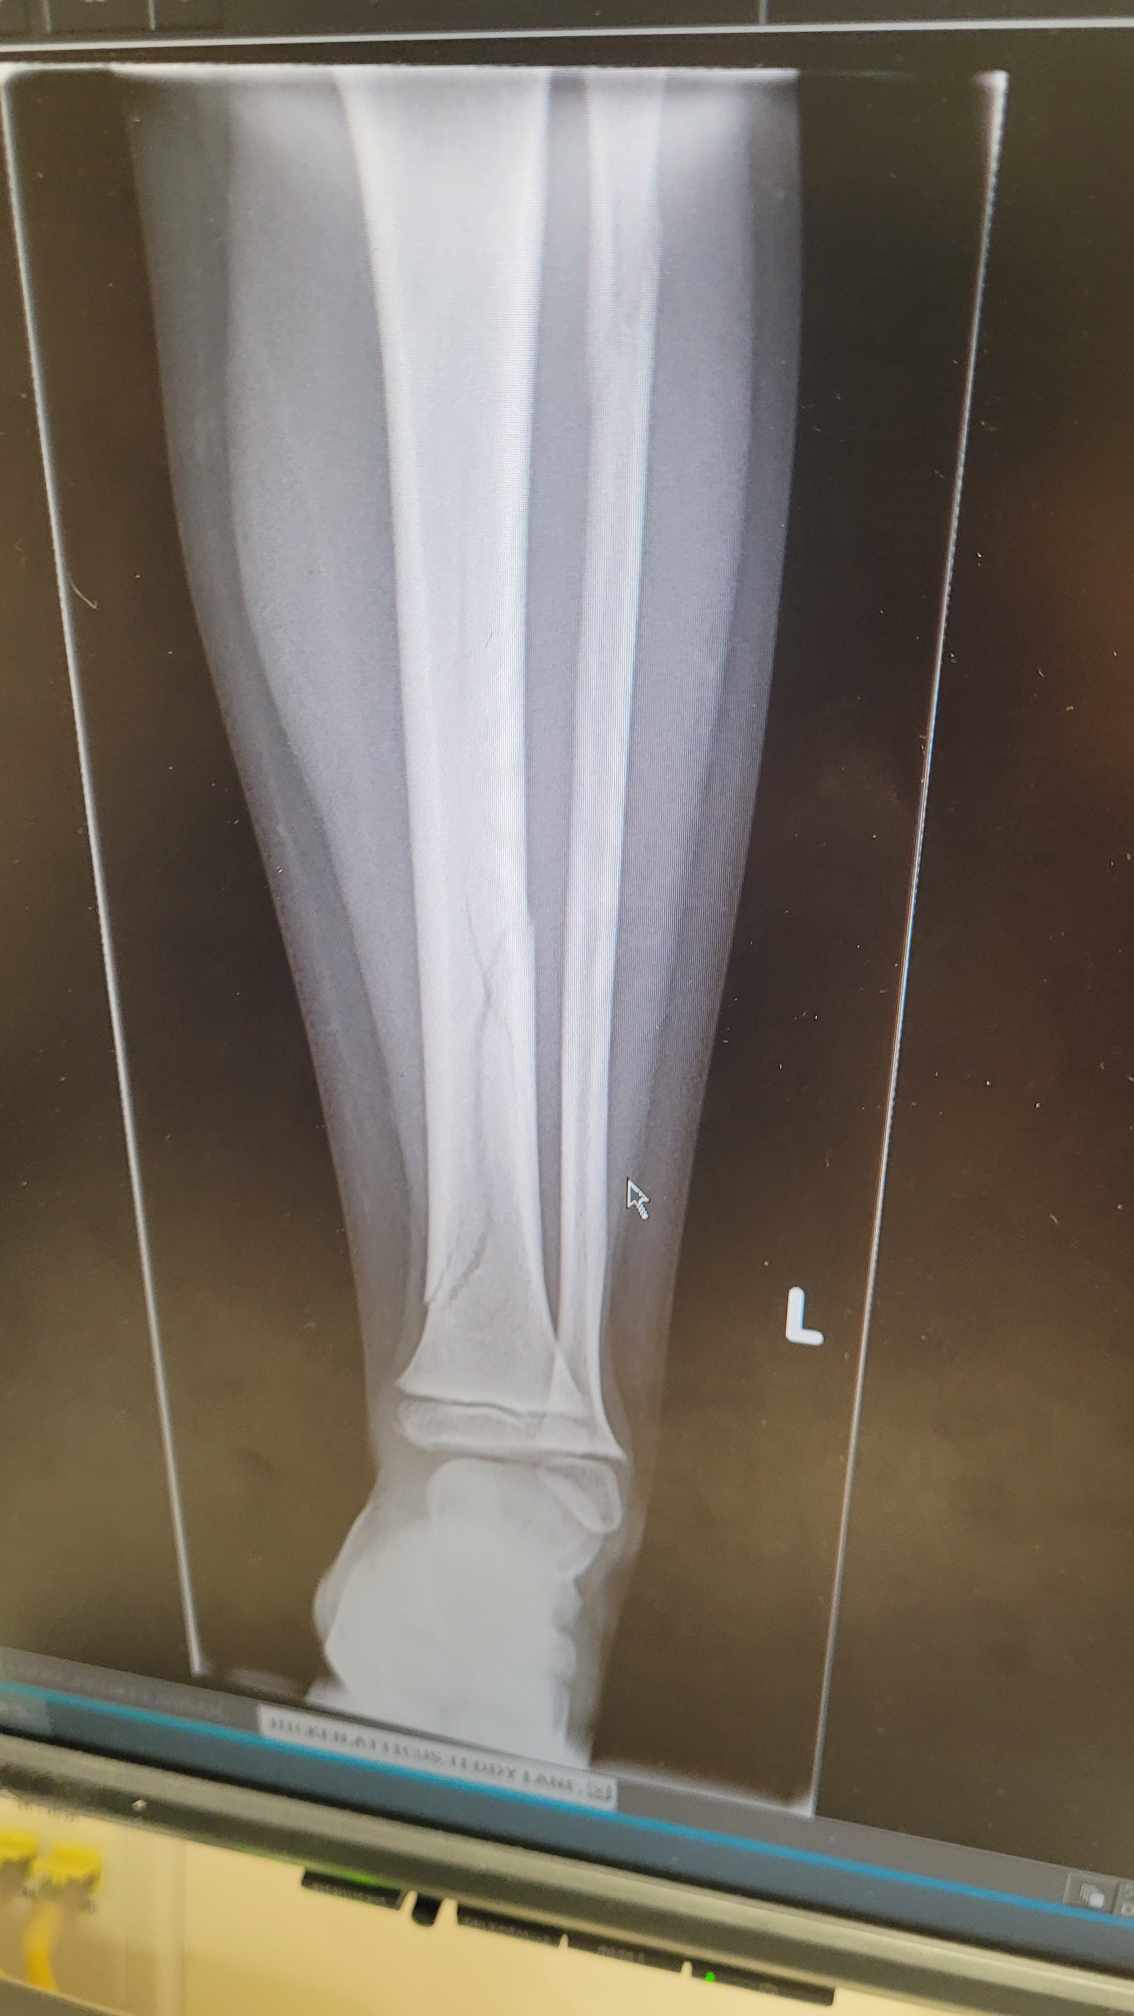

Our poor little Atticus. As a rambunctious boy he jumped off the cabinet and fractured ( for those that don’t know a fracture is a break in the medical world) hit the bean bag for his landing but his leg took the blunt of the force. Logical to think a bean bag landing is safe . LOL I always thought a fracture was like a splinter but doctors like to use fracture to sound more professional than saying broke. It has two cracks in the tibia so full leg cast over the knee, no weight for a month and it should heal just fine. That has to hurt. So lucky not to have surgery with bolts or plates.

FULL DISCLOSURE- I have never broke ( no fancy words for me) a single bone in my body. I have only received minimal stitches in my life. I am going to say 10 max. I have had one “surgery” with a small incision at the belly button for a biopsy. That is it. So I really can’t say what kind of pain one would experience with a break but it makes me shiver to think about it. Poor Atti ! The pain would be worse than childbirth and near touching on Gout pain I assume.

You can see the break quite easily.

The cast is made over the knee so he can’t bend it. A plan I am sure so he can not put his weight on it. The first time going to the washroom will be interesting. Plaster of Paris must be in short supply with the way they made this cast. Supposedly people say under the cast gets itchy and drives people nuts.

He will like the attention for a day or so then reality will sink in and it will suck. Jess & Pen will be tired. Lots of IPad and Tv watching.